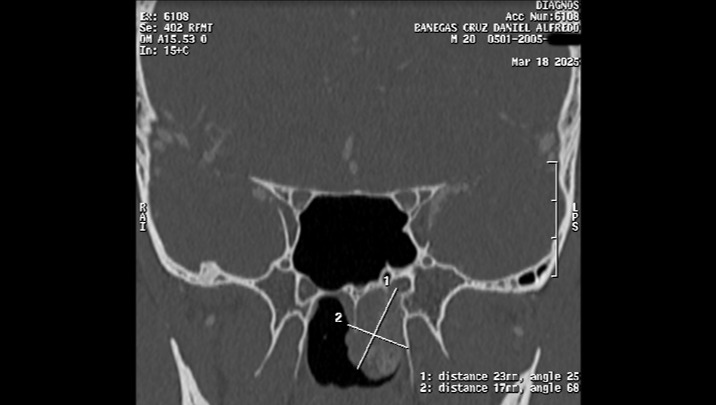

As some of you are already aware, my son Daniel Alfredo (20 years old), is about to undergo urgent surgery due to a (benign) Nasopharyngeal Angiofibroma tumor (in the upper area of the throat, behind the nose), and the medical expenses are quite high, around $8,000.00, which covers hospitalization, medical fees, medications, studies prior to surgery, and transfusions (if needed).